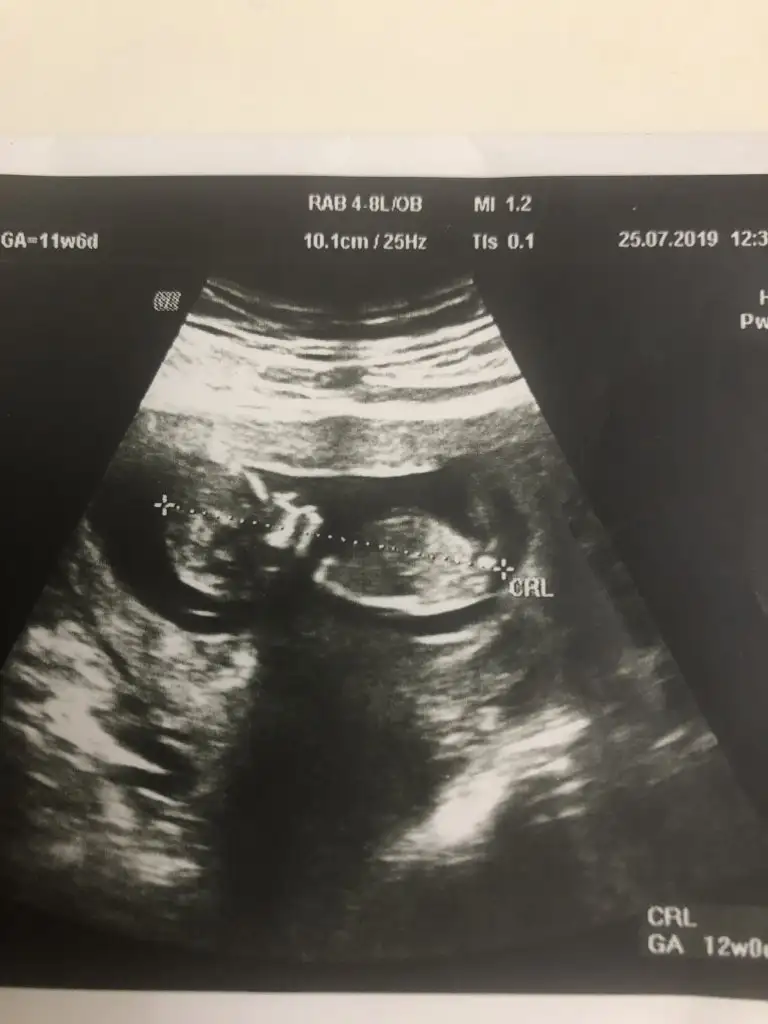

Normalde 10+5’im ama biraz hızlı büyümüşüm, bugün kontrolde 11+5 çıkınca enseme burnuma bile bakıldı. Poz verdim sizlere. Sizce kız mıyım erkek mi?

Kız olduğunu düşüyorum senin tatlılıkTeyzelerim,